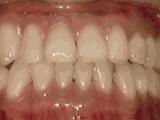

5、开合,上下牙齿没有接触没有咬合,前牙没有咬合功能,无法咬切食物,会影响发音,经过矫正后的牙齿是这样的~

6、深覆合,咬牙时上牙全部覆盖下牙或覆盖过多;常出现,面容下三分之一过短,微笑时上颌露出牙龈过多,影响美观,经过矫正的牙齿是这样的~

7、牙列稀疏,个别牙齿先天缺失,导致牙列稀疏,散在间隙影响美观影响咬合,经过矫正后的是这样的~

8、前牙反合,俗称“地包天”,也就是咬牙时,下牙盖住上牙,正常情况应该是上牙盖住下牙,经过矫正后的牙齿可以变成这样的~